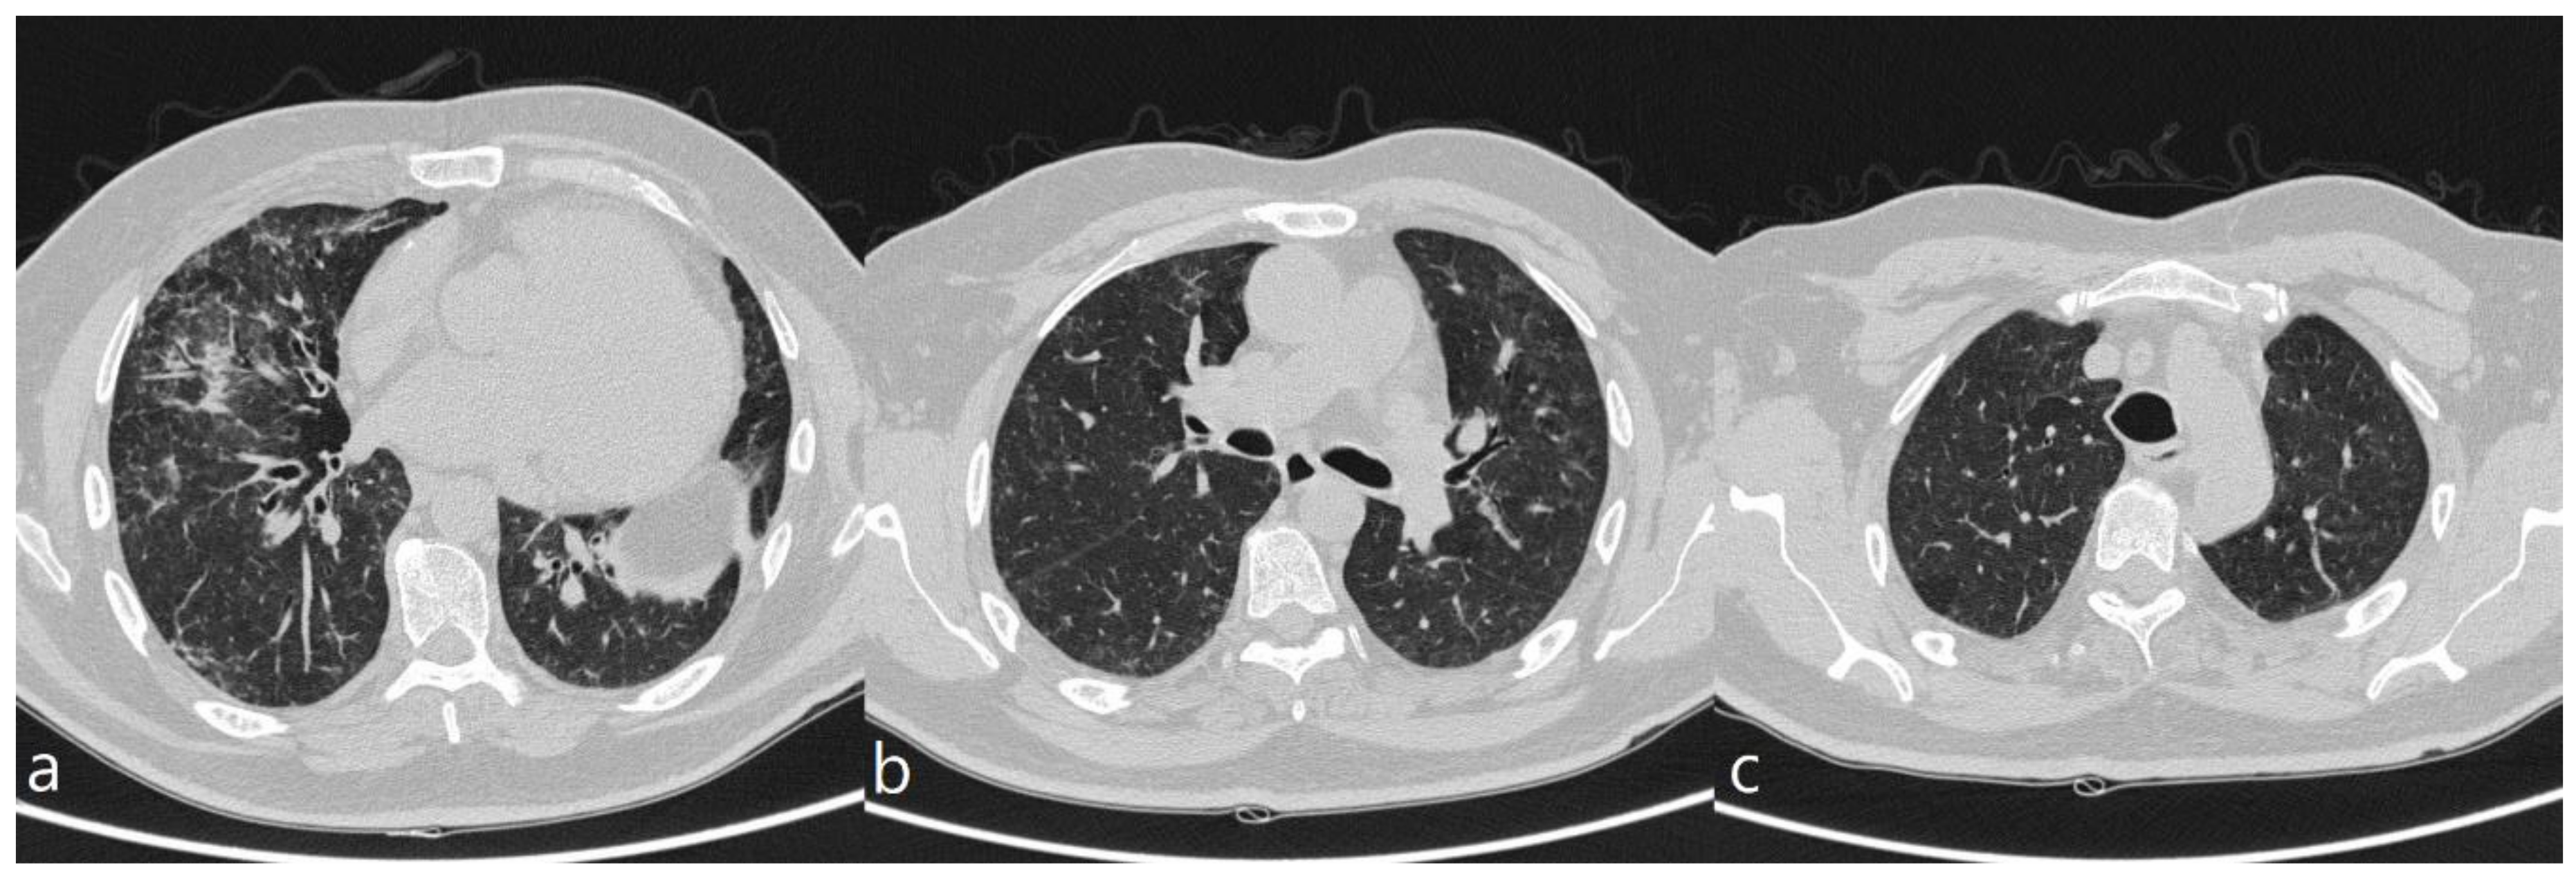

| HRCT Pattern | Associated Drugs |

|---|---|

| Fibrotic pattern | Nitrofurantoin (chronic toxicity), methotrexate, sulfalazina, rituximab, tocilizumab, bleomycin, busulfan, cyclophosphamide (chronic toxicity), amiodarone (form with fibrous course), tocainide, cocaine |

| Organizing pneumonia | Nitrofurantoin (chronic toxicity), methotrexate |

| Mosaic pattern | Nitrofurantoin (acute toxicity), methotrexate, sulfalazina |

| Isolated ground glass | Rituximab, tocilizumab, cyclophosphamide (acute reaction), amiodarone (initial stage), cocaine |

| Alveolar hemorrhage | Penicillamine, rituximab, cocaine |

| Pulmonary edema | Acetyl-salicylic acid, mitomycin |

| Pleural effusion | Sulfonamides, methotrexate |